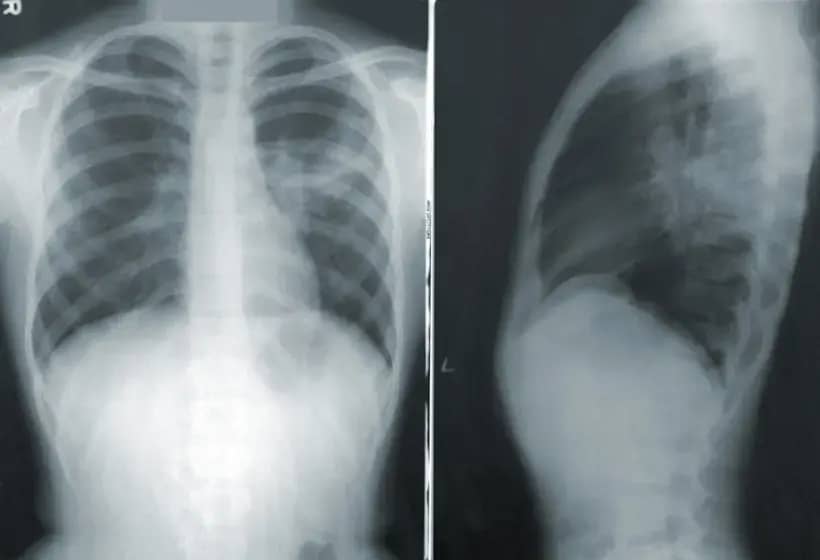

Vrste pneumonije i komplikacije

Pneumonija može biti bakterijska (čest uzročnik Streptococcus pneumoniae), virusna (npr. grip, SARS‑CoV‑2, RSV), gljivična ili atipična (Mycoplasma, Chlamydia). Najčešće komplikacije su pleuralni izliv, apsces pluća, sepsa, meningitis i respiratorna insuficijencija. Teška bakterijska upala pluća može biti smrtonosna, zato je rana dijagnoza i liječenje važno.